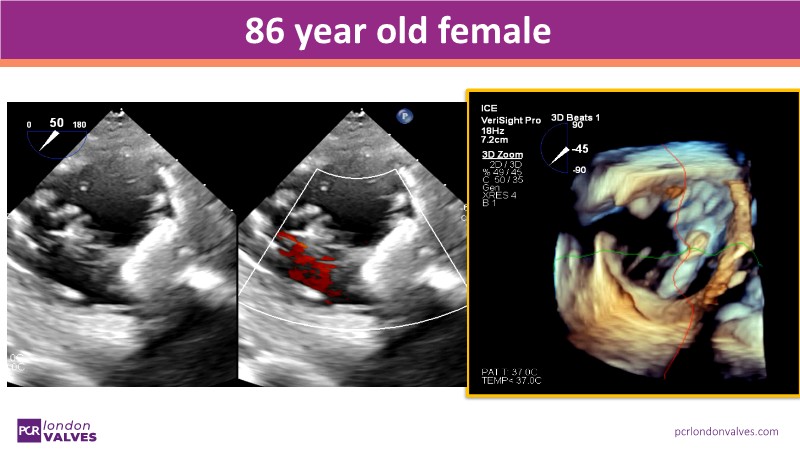

This PCR London Valves 2025 session explores how 3D TEE, 3D intracardiac echocardiography (ICE), and DeviceGuide technology sharpen procedural accuracy, strengthen operator confidence, and streamline decision-making in real time.

You’ll see how clearly defined team roles enhance both safety and efficiency, and how thoughtful workflow integration can reduce anesthesia needs and shorten procedures, without compromising results.

The session also includes detailed case analyses—such as Mitral TEER and LAA closure—and dual perspectives from both proceduralists and imagers.